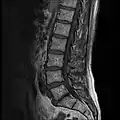

MRI

MRI lumbar spine with degeneration (sagittal T2 FRFSE)

MRI lumbar spine with degeneration (sagittal T1 FSE)

MRI lumbar spine with degeneration (sagittal FAST STIR)- MRI lumbar spine pre-hemilaminectomy (sagittal T2 FRFSE)